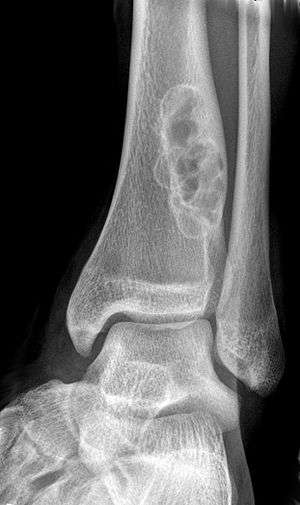

X-ray of nonossifying fibroma of distal tibia.

A nonossifying fibroma (also called fibroxanthoma) is a fibrous bone lesion that is usually asymptomatic and discovered as an incidental finding on x-ray. It is the most common benign bone tumor in children and adolescents. However, it is controversial whether it represents a true neoplasm or rather a developmental disorder of growing bone. Radiographically, the tumor presents as a well marginated radiolucent lesion, with a distinct multilocular appearance. These foci consist of collagen rich connective tissue, fibroblasts, histiocytes and osteoclasts. They originate from the growth plate, and are located in adjacent parts of the metaphysis and diaphysis of long bones, most often of the legs. No treatment is needed in asymptomatic patients and spontaneous remission with replacement by bone tissue is to be expected.